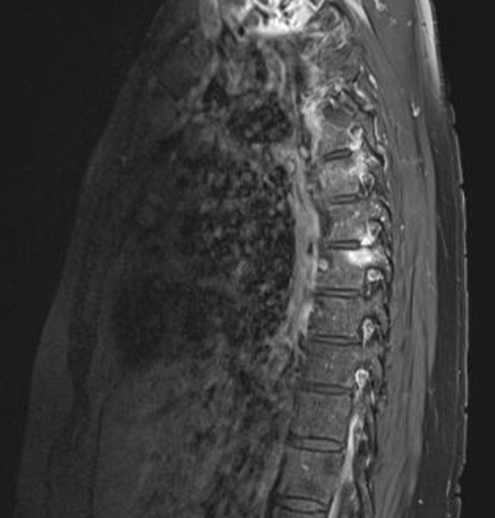

2019 stellte sich die damals 59 Jahre alte Patientin erstmals bei Dr. Christina Binder-Jovanović, Rheumatologin aus München, vor. Ein MRT ergab eine erosive Osteochondrose im Bereich LWK5/S1 mit einem Bandscheibenprolaps. Die Patientin äußerte den Wunsch eines Medikamentenwechsels, da sie durch die MTX-Therapie unter einer leichten Abgeschlagenheit und Kopfschmerzen litt sowie häufig an Infekten der oberen Luftwege und Harnwege erkrankte. Dr. Binder-Jovanović empfahl jedoch zunächst, die MTX-Therapie mit einer reduzierten Dosis von 10 mg wöchentlich oral weiterzuführen. Durch die Dosisreduktion kam es jedoch zu einem erneuten Schub: Anfang 2020 kehrte die Psoriasis in voller Stärke zurück: Ihr PASI (Psoriasis Area and Severity Index) stieg von 4,0 im Januar auf 7,2 im Februar stark an. Auch der Genitalbereich war betroffen.

Zusätzlich klagte die Patientin über 7 schmerzende Gelenke (Tender Joint Count (TJC): 7). Die Schmerzen gab sie auf der Visuellen Analog Skala (VAS) mit 70 von 100 an. Besonders nachts waren die Rückenschmerzen quälend, während Bewegung tagsüber Linderung brachte. Die Blutsenkung lag bei 27 mm/h und der CRP-Wert bei 1,13 mg/dl. Rheumafaktor und CCP-AK waren nicht erhöht. Die Patientin war HLA-B27 negativ. Eine Untersuchung der Brustwirbelsäule im Februar 2020 zeigte eine Hyperämie am Kostotransversalgelenk und anteilig am Kostovertebralgelenk von BWK 7 links mit Ödem im angrenzenden Pedikel sowie diskrete Veränderungen auch an BWK 5 und eine diskale Enthesitis im Bereich BWK 5/6 rechts.

Abb. 1: MRT-Aufnahme vor der Therapie mit Taltz®